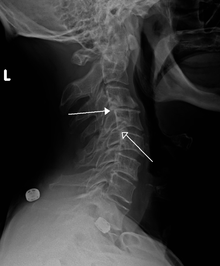

A retrolisthesis is a posterior displacement of one vertebral body with respect to the adjacent vertebrae to a degree less than a luxation (dislocation). Clinically speaking, retrolisthesis is the opposite of spondylolisthesis (anterior displacement of one vertebral body on the subjacent vertebral body), and is also called retrospondylolisthesis.[1] Retrolistheses are most easily diagnosed on lateral x-ray views of the spine. Views, where care has been taken to expose for a true lateral view without any rotation, offer the best diagnostic quality.

Pain may be experienced as a result of irritation to the sensory nerve roots by bone depending on the degree of displacement and the presence of any rotatory positioning of the individual spinal motion segments. The soft tissue of the disc is often caused to bulge in retrolistheses. These cannot be determined by plain films, as the x-ray passes through the soft tissue. A study by Giles et al., stated that Sixteen of the thirty patients (53%) had retrolisthesis of L5 on S1 ranging from 2–9 mm; these patients had either intervertebral disc bulging or protrusion on CT examination ranging from 3–7 mm into the spinal canal. Fourteen patients (47%) without retrolisthesis (control group) did not show any retrolisthesis and the CT did not show any bulge/protrusion. On categorizing x-ray and CT pathology as being present or not, the well positioned i.e. true lateral plain x-ray film revealed a sensitivity and specificity of 100% ([95% Confidence Interval. = [89%–100%]) for bulge/protrusion in this preliminary study.” (7)